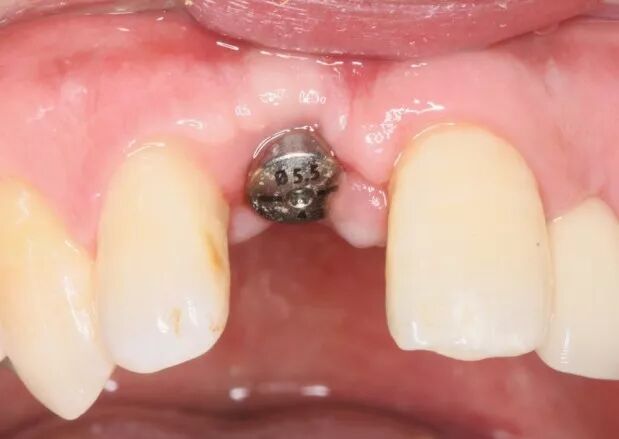

種植及成骨效果